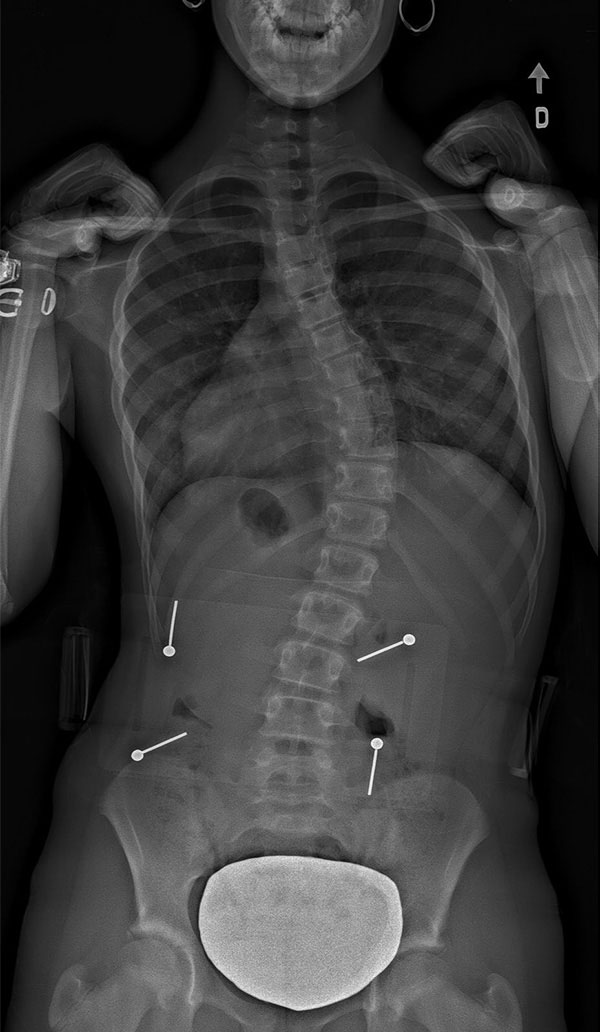

Scoliosis is a 3D deformation of the spine involving torsion which translates into a lateral curvature of over 10° as well as abnormal rotation of the vertebrae. Often described as an S-shaped deformation, a scoliotic spine more accurately resembles a spiral staircase.

Thoracic scoliosis (dorsal) – same level as the ribcage.